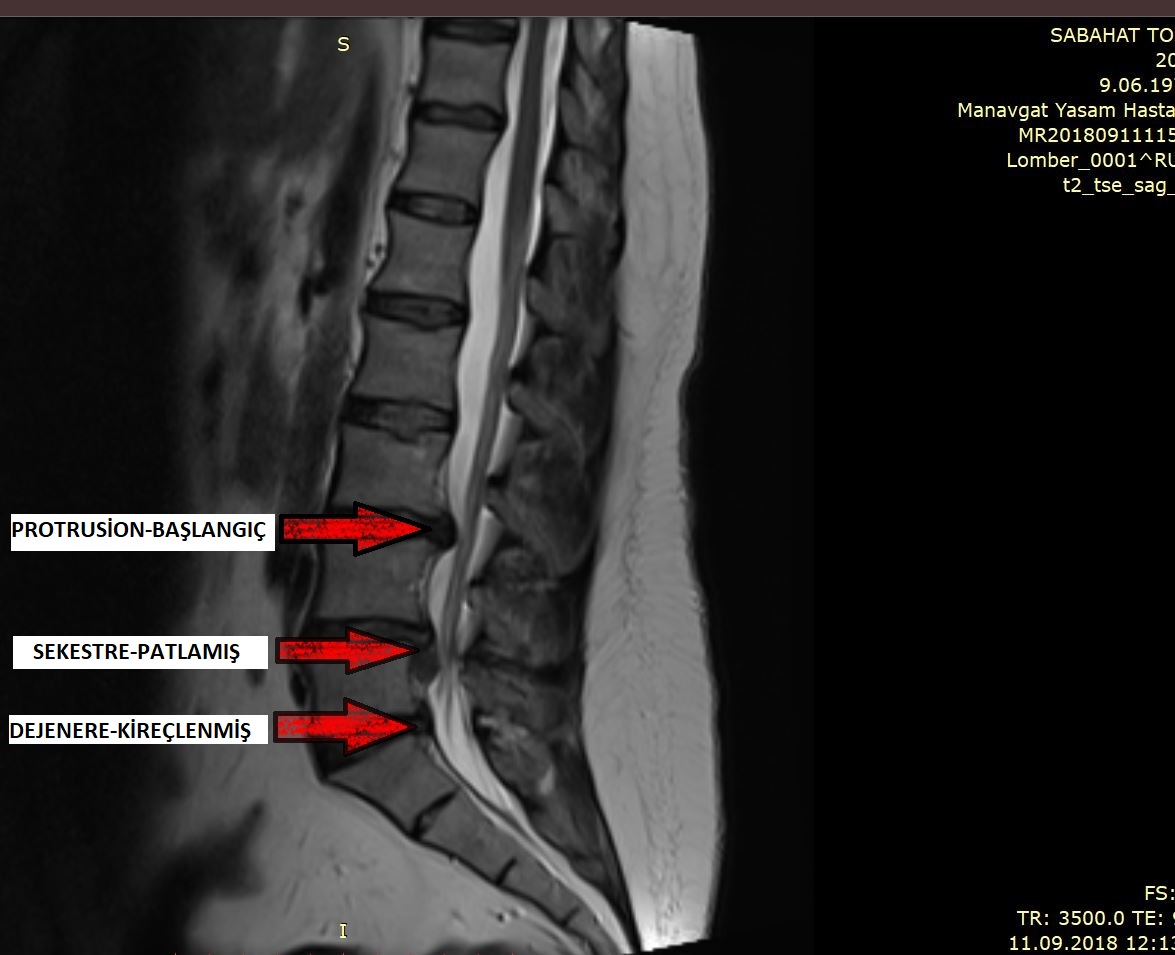

Omurganız jöle benzeri bir maddeden yapılmıştır. Yumuşak disklerle tamponlanmış olan omurlar 26 kemikten oluşur. Bu diskler omurganızı hareket ettirmenize ve eğilmenize izin veren şeydir. Fakat iki omurga arasındaki bir disk yerinden çıkmaya başlarsa, çevredeki sinirleri tahriş edebilir ve aşırı ağrıya neden olabilir. Bu da bel fıtığı dediğimiz durumu açıklar.

Bel fıtığı çoğu zaman, kademeli, yaşlanma ile ilişkili yıpranma ve disk dejenerasyonu adı verilen gözyaşıdır. Yaşlandıkça, omurilik diskleriniz su içeriğinin bir kısmını kaybeder. Bu onları daha az esnek ve daha küçük bir gerilme veya bükülme ile yırtmaya daha eğilimli yapar.